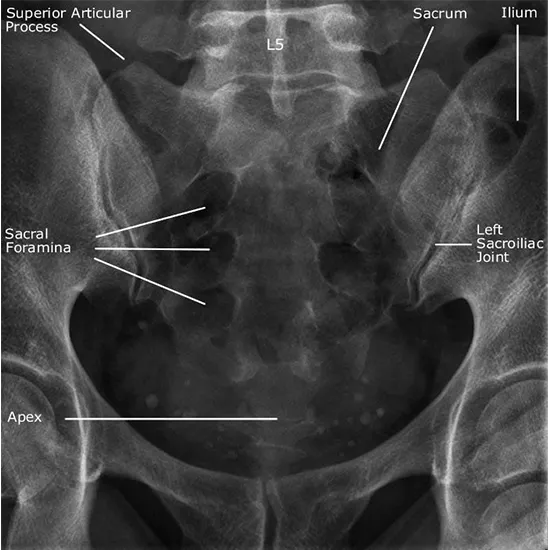

The lateral view of the Sacrum is the view that is utilized to demonstrate the rear portion of the spine from the side.

The lateral view of the Sacrum is often used with the AP projection, but it can also be used on its own, depending on how the department works. It helps to see what's wrong with the Sacrum and coccyx and looks into the cause of both short-term and long-term pain in those areas.